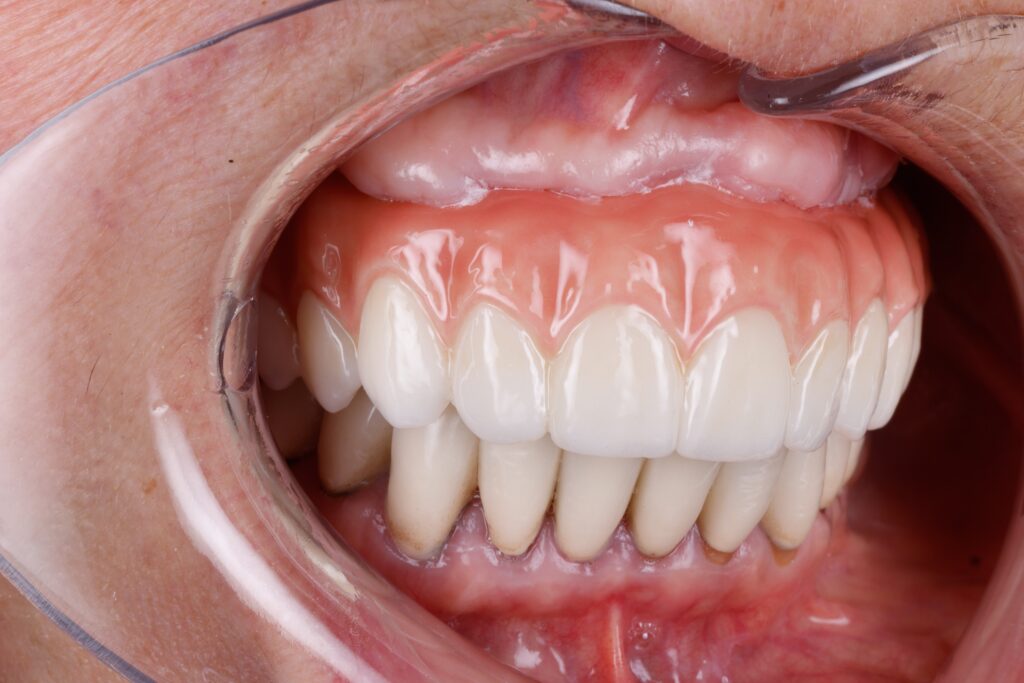

Full Arch Fixed Teeth

For patients missing many teeth, implant-supported overdentures offer a secure, affordable alternative to traditional dentures. Anchored on 2–4 implants, they stay firmly in place, resist slipping, and help preserve bone health. This solution improves comfort, enhances speech, and allows you to eat, chew, and taste food naturally. Reliable, stable, and confidence-boosting.

Before

After